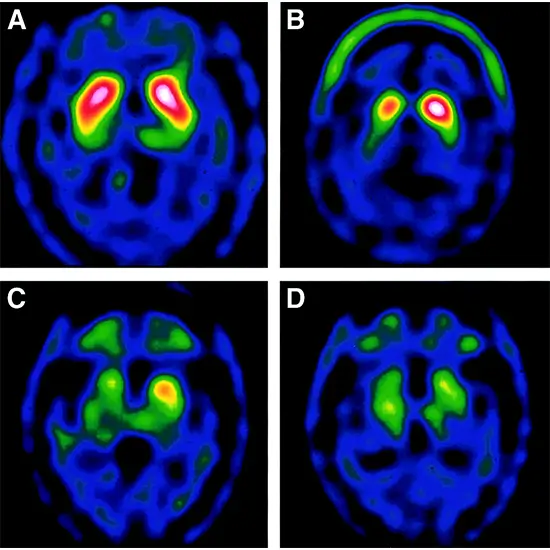

Trodat Brain Scan is an advanced nuclear medicine scan that is used to diagnose Parkinson’s disease. It helps in distinguishing between Parkinson’s disease and essential tremor because the symptoms of both disorders are the same. It is mainly recommended for patients with symptoms of Parkinson’s disease such as tremors, stiff muscles, compromised posture, compromised gait, speech and writing changes, etc.

The Trodat Brain Scan procedure takes around 30-45 minutes. To perform the test, isotope radiation will be administered intravenously to the patient to check the dopamine level Gamma Camera will be used to take the picture of the brain.

The result shows the dopamine (happy hormone) level in the brain.